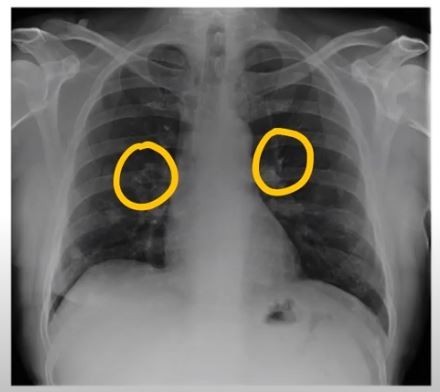

폐암은 위암, 갑상선암 다음으로 3번째로 발병 빈도가 높은 3대 암 중 한 가지인데요. 폐암은 재발과 전이까지의 빈도도 잦은지라 완치가 어렵다고 하며 폐암 발병 초기에는 거의 증상이 없을 수가 있어 수술이 불가능한 3기, 혹은 4기에 주로 진단된다고 해요.

폐암 초기증상 폐암 4기에 이르게 되면 5년 생존률이 30% 대로 감소하게 된다고 해요. 그리하여 폐암은 암 질병이자 중 사망자 비율이 가장 높은 것으로 나타나고 있어요.

폐암은 사망률 2위를 차지하고 있는 간암에 비해 무려 2배에 가까운 사망률을 보이고 있다고 합니다. 이렇게 치명적인 폐암에 대해 미리 알고 대처하는 것이 바람직할 것 같아요. 아래에서는 폐암이라 판단해 볼 수 있는 그 초기증상에 대해 간단히 설명드릴게요.